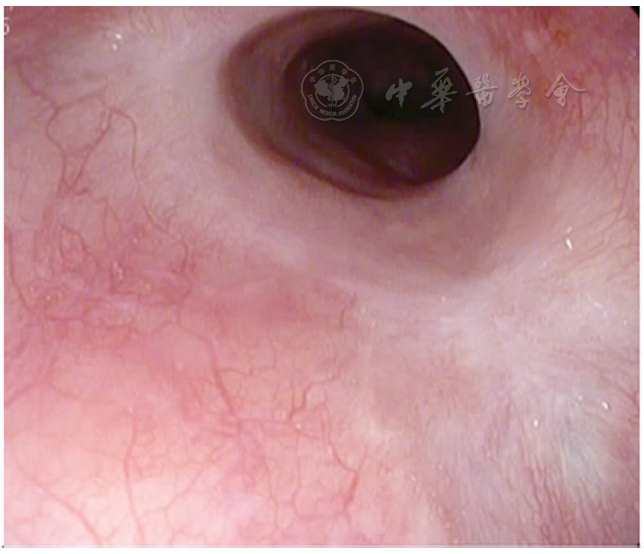

图8 术中止血后再次胃镜检查

图9 术后5个月ESD处黏膜瘢痕样改变